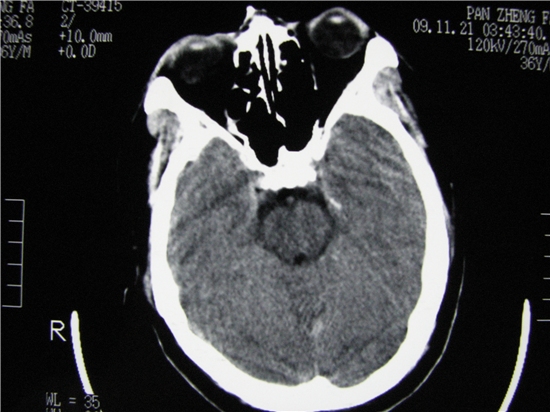

标题: CT23231:男 32岁 车祸伤,鼻腔内出血明显。 [打印本页]

标题: CT23231:男 32岁 车祸伤,鼻腔内出血明显。

额窦里是什么,骨窗怎么不清晰,是不窗宽窗位的事。

软组织及额窦内异物

额窦内及额部软组织内可见多发游离类骨质密度影,考虑额骨骨折可能。

鼻骨层面较少,无法判断鼻骨。

额窦内应该是正常的,和体位有关系,当你用三位重建就知道了

额窦致密骨瘤,前额部及右顶部头皮损伤伴异物存留

左侧额骨、鼻骨骨折,头面部软组织肿胀。

左侧额骨、鼻骨骨折,额窦内的应该是游离骨块

额窦致密骨瘤,